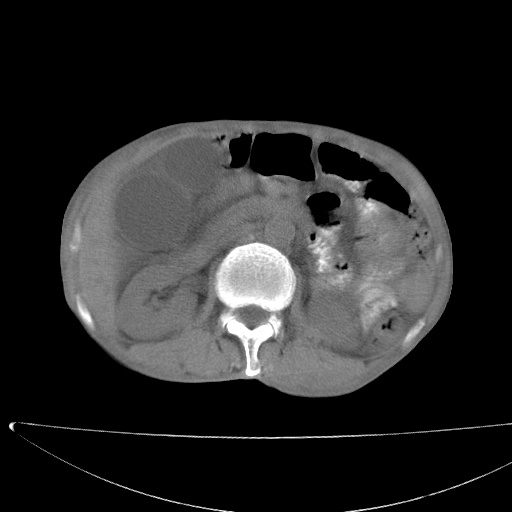

标题: CT17147:男70岁,上腹部不适1月。 [打印本页]

患者男70岁,上腹部不适1月。8年前有胃癌手术史。余病史不祥。

1)胃癌术后,复发不排除。

2)肝脏转移瘤。

3)肝脏钙化灶。

4)胆囊增大。

5)腹膜后多发性淋巴结转移。

6)腹水。

7)右侧少量胸水。

建议:增强扫描。